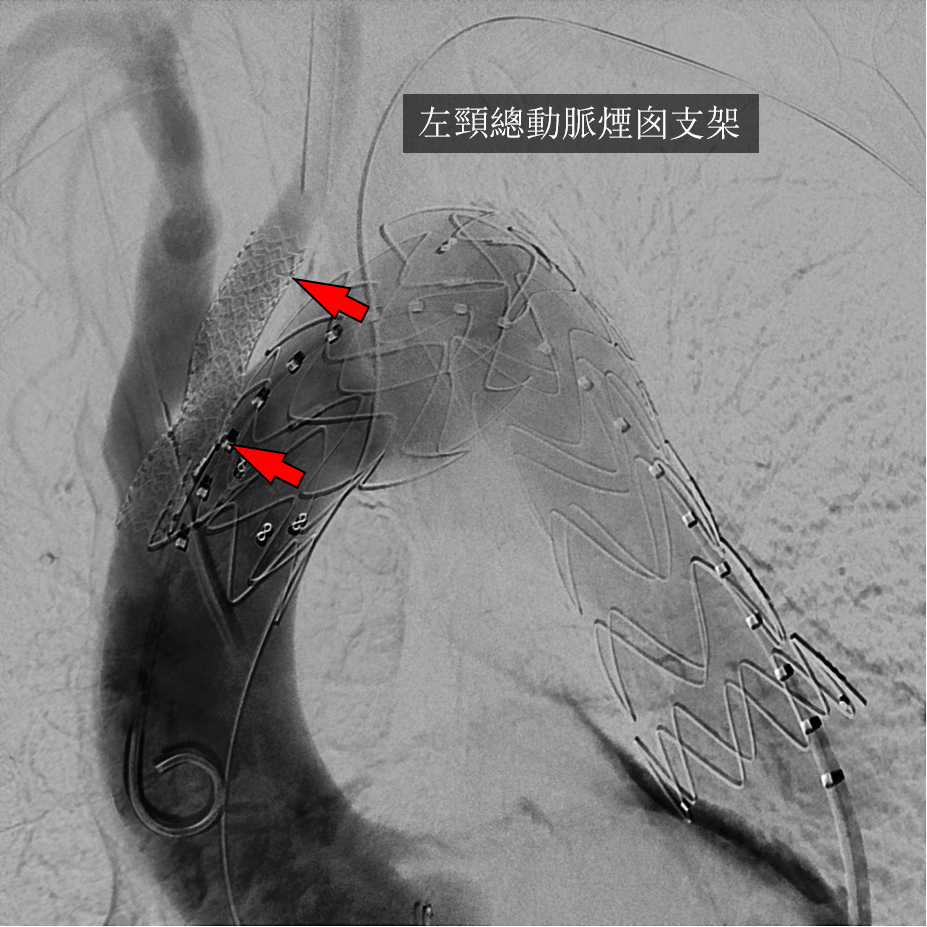

腔内技术的“野路子”

随着腔内技术的发展,烟囱(Chimney)技术和术中开窗(On-Table Fenestration)曾一度流行。然而,这些技术往往伴随着较高的内漏(Endoleak)发生率和支架闭塞风险,且操作复杂,极度依赖术者的经验。

破局利器

TBE支架的设计哲学与操作精髓

TBE支架的出现,解决了“等待时间”与“解剖适应”之间的矛盾。

★ 结构设计

TBE并非单一的直管状支架,而是一个由主动脉主体(Aortic Component)、分支组件(Side Branch Component)和主动脉延长段(Aortic Extender)组成的系统。

内部端口(Internal Portal): 主体支架上的特殊设计,允许分支支架在此固定,实现密封。

柔软性: 分支设计具有极佳的柔顺性,以适应弓部的弯曲血流动力学。